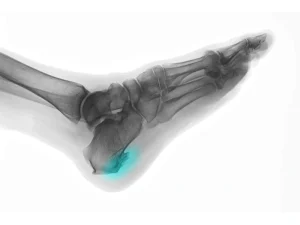

علائم مهم خار پاشنه در کودکان که نباید نادیده بگیرید + درمان

خار پاشنه در کودکان مشکلی است که میتواند باعث درد هنگام راه رفتن و بازی کردن شود. این مشکل معمولاً به دلیل فشار زیاد روی پاشنه یا کفش نامناسب ایجاد